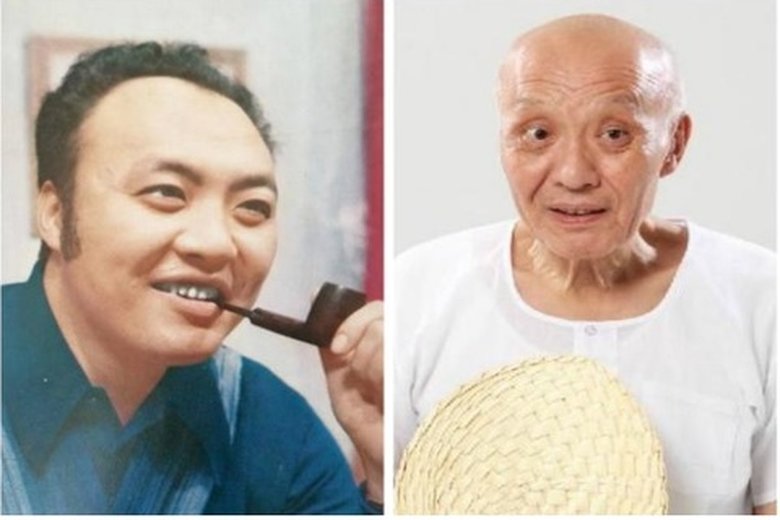

巨星殞落 鳳飛飛肺癌病逝

2012-02-13 21:03:52新聞頭條,帶您關心,又是一代巨星殞落的消息,帽子歌后鳳飛飛驚傳病逝,享年六十歲。其實鳳飛飛早在一月三日,就已經因為肺癌四期病逝香港,但由於體貼親友,生性低調,直到病逝後40天,才由鳳飛飛的獨生子同步通知至親,獨子同時也在昨天(12日)親自護送母親的骨灰到桃園大溪,一代歌后,最後落葉歸根在摯愛的家鄉。

鳳飛飛肺癌逝 醫:晚期存活不到一年

2012-02-15 21:18:50帽子歌后鳳飛飛因為肺癌辭世,原訂去年開唱的演唱會,因聲音沙啞而取消,其實那時的她已經是肺癌第四期,癌細胞轉移淋巴,壓迫到聲帶;肺癌又稱沉默殺手,初期根本沒有徵兆,胸腔科醫師提醒,尤其是50歲以上的民眾,一定要定期到醫院作檢查。

《麻辣鮮師》的老趙乾德門 肺癌病逝享壽74歲

2018-02-05 11:26:45出演《麻辣鮮師》的老趙出名的資深藝人乾德門,今凌晨4點病逝新店同仁醫院,享壽74歲,3個月前在家中浴室因呼吸困難,送進加護病房插管治療,情況未有好轉,臥病期間意識清醒,因插管無法正常溝通,病況亦無明顯改善,轉至住家附近療養院。